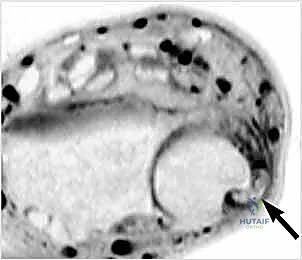

- MRI: This is our most sensitive and specific imaging modality for detecting ECU subluxation.

FIG 3 • A. This MRI scan shows a “perched” ECU tendon, out of the dorsal ulnar groove. Notice the increased signal in the tendon substance.

To maximize sensitivity, MRI studies should ideally be performed with both wrists positioned in pronation, neutral, and supination, allowing for side-by-side comparison with the asymptomatic wrist and dynamic assessment of the ECU's position relative to the ulnar osseous groove. While the actual subsheath tear may or may not be directly visualized, inflammation and partial interstitial tendon disruption are often evident.